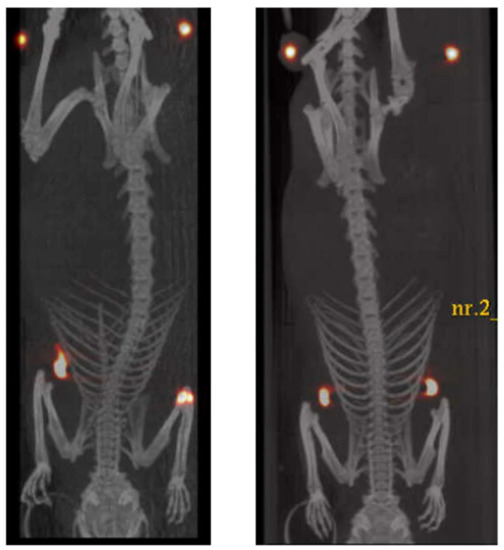

| Fluorine-substituted TSPO ligand | 18F | PET | Detection of neuroinflammation, neurodegeneration, and tumor progression | Ex vivo: ICR mice In vivo: U87-MG xenografted Balb/c nu/nu mice | [17] | |

| USPIONs | Cyanine 5.5 fluorescent dye | NIR optical imaging | Detection of glioblastoma exploiting TSPO targeting | In vitro: U87-MG glioblastoma cells and PC3 prostate cancer cells In vivo: Balb/c athymic mice | [38] | |